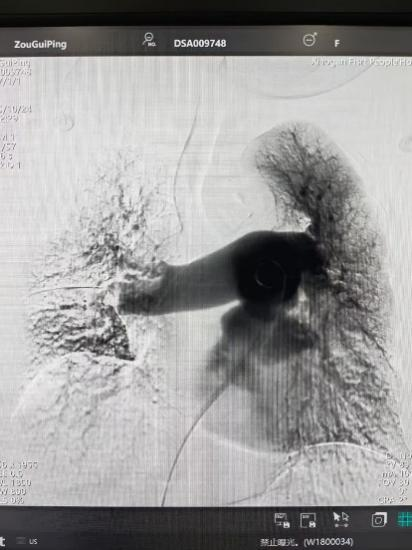

術(shù)后

手術(shù)在局部麻醉下進行,團隊通過股靜脈穿刺,將專用抽栓導管精準送達肺動脈栓塞部位,利用負壓抽吸技術(shù)成功清除大量血栓;隨后,在血栓局部精準灌注溶栓藥物,進一步溶解殘余血栓,恢復肺部血流灌注;同時,為防止下肢深靜脈血栓再次脫落引發(fā)肺栓塞,團隊為患者置入下腔靜脈濾器,整個手術(shù)歷時約1小時。術(shù)后,鄒婆婆呼吸困難癥狀即刻得到緩解,血氧飽和度顯著提升,右心負荷明顯減輕,目前身體狀況正在逐步恢復中。